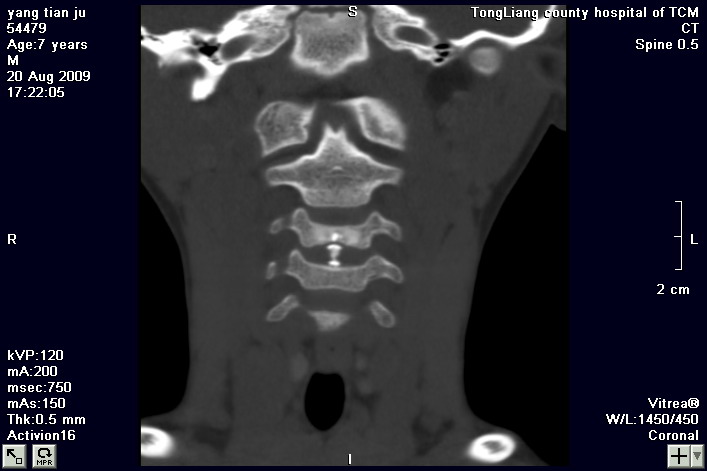

标题: PED2853:颈3/4椎间盘内高密度钙化灶,请各位会诊. [打印本页]

标题: PED2853:颈3/4椎间盘内高密度钙化灶,请各位会诊.

患儿,7岁,颈部疼痛3天,颈部活动受限.

本例应该是典型的儿童钙化性椎间盘病。

儿童钙化性椎间盘病发病年龄多在5~12岁,男女比例相当,大多数患儿发病主要表现为颈部疼痛,伴活动受限。少数有吞咽不适或肢体瘫痪。有一部分患儿无症状,是在其它检查时发现。病因尚不完全明了,可能的有:1、感染。2外伤。

儿童颈椎椎间盘钙化系一良性自限性疾病,可见于颈、胸、腰椎,以颈椎为多发,腰椎少见,多为单发。钙化位于髓核,也可累及软骨板和纤维环引起钙化主要发生于c 4~7  的髓核位于椎间隙正中或偏后,少数向前疝出,以后部多见,呈梭状、盘状、团块状或半环状;(2)颈椎生理曲度变直,椎间隙正常或增宽;(3)相邻椎体可变扁,局部凹陷变形,椎体前下缘鸟嘴状增生,或呈钳口状改变,椎前软组织增厚及环枢椎半脱位;(4)ct可清晰显示椎间盘髓核 位置的钙化灶及经破裂的纤维环向椎管内突出。(5)mri,钙化在t1及t2加权像上均呈低信号,并可见脊髓组织内异常信号。